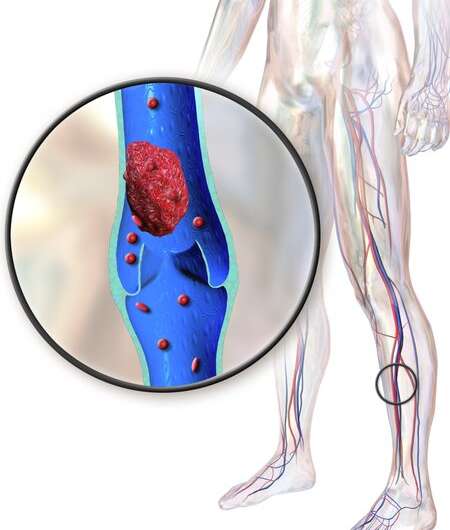

vein thrombosis deep dvt danger clot blood prevention

dvt thrombosis vein

thrombosis vein dvt blood